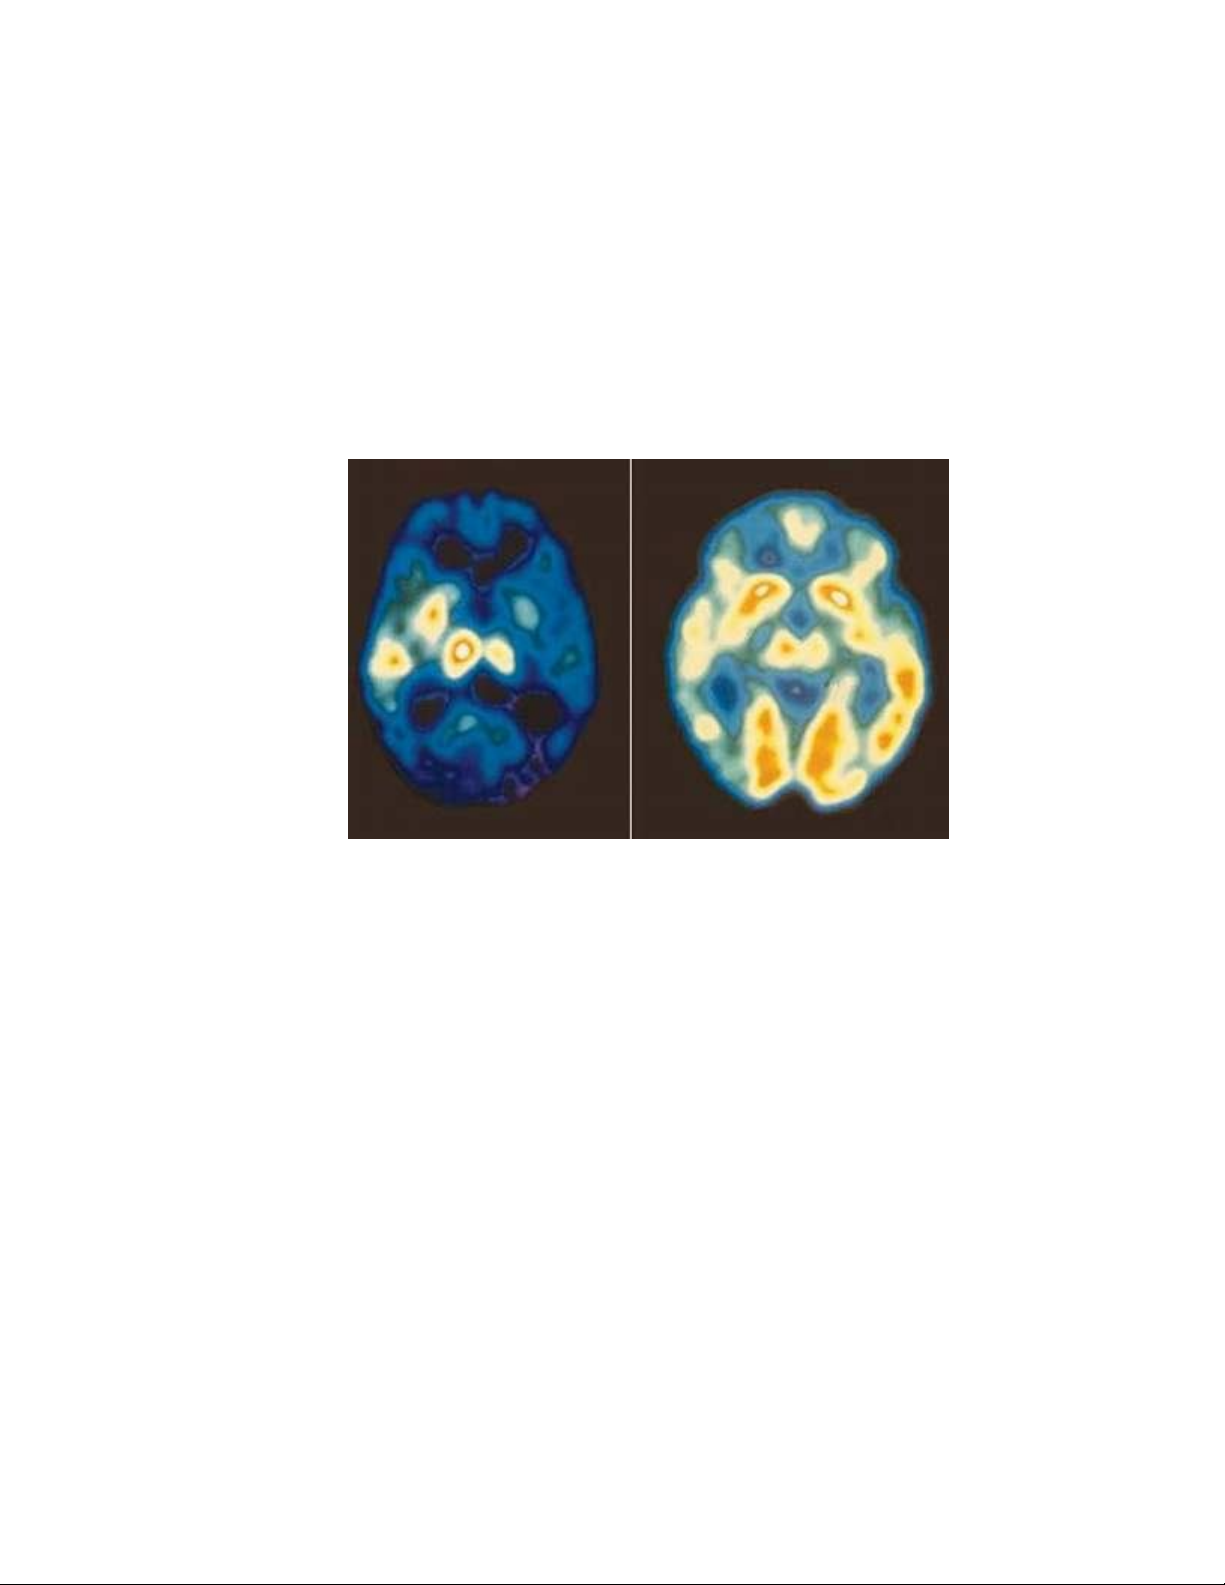

Não của người mắc chứng trầm cảm. - Não người bình thường.